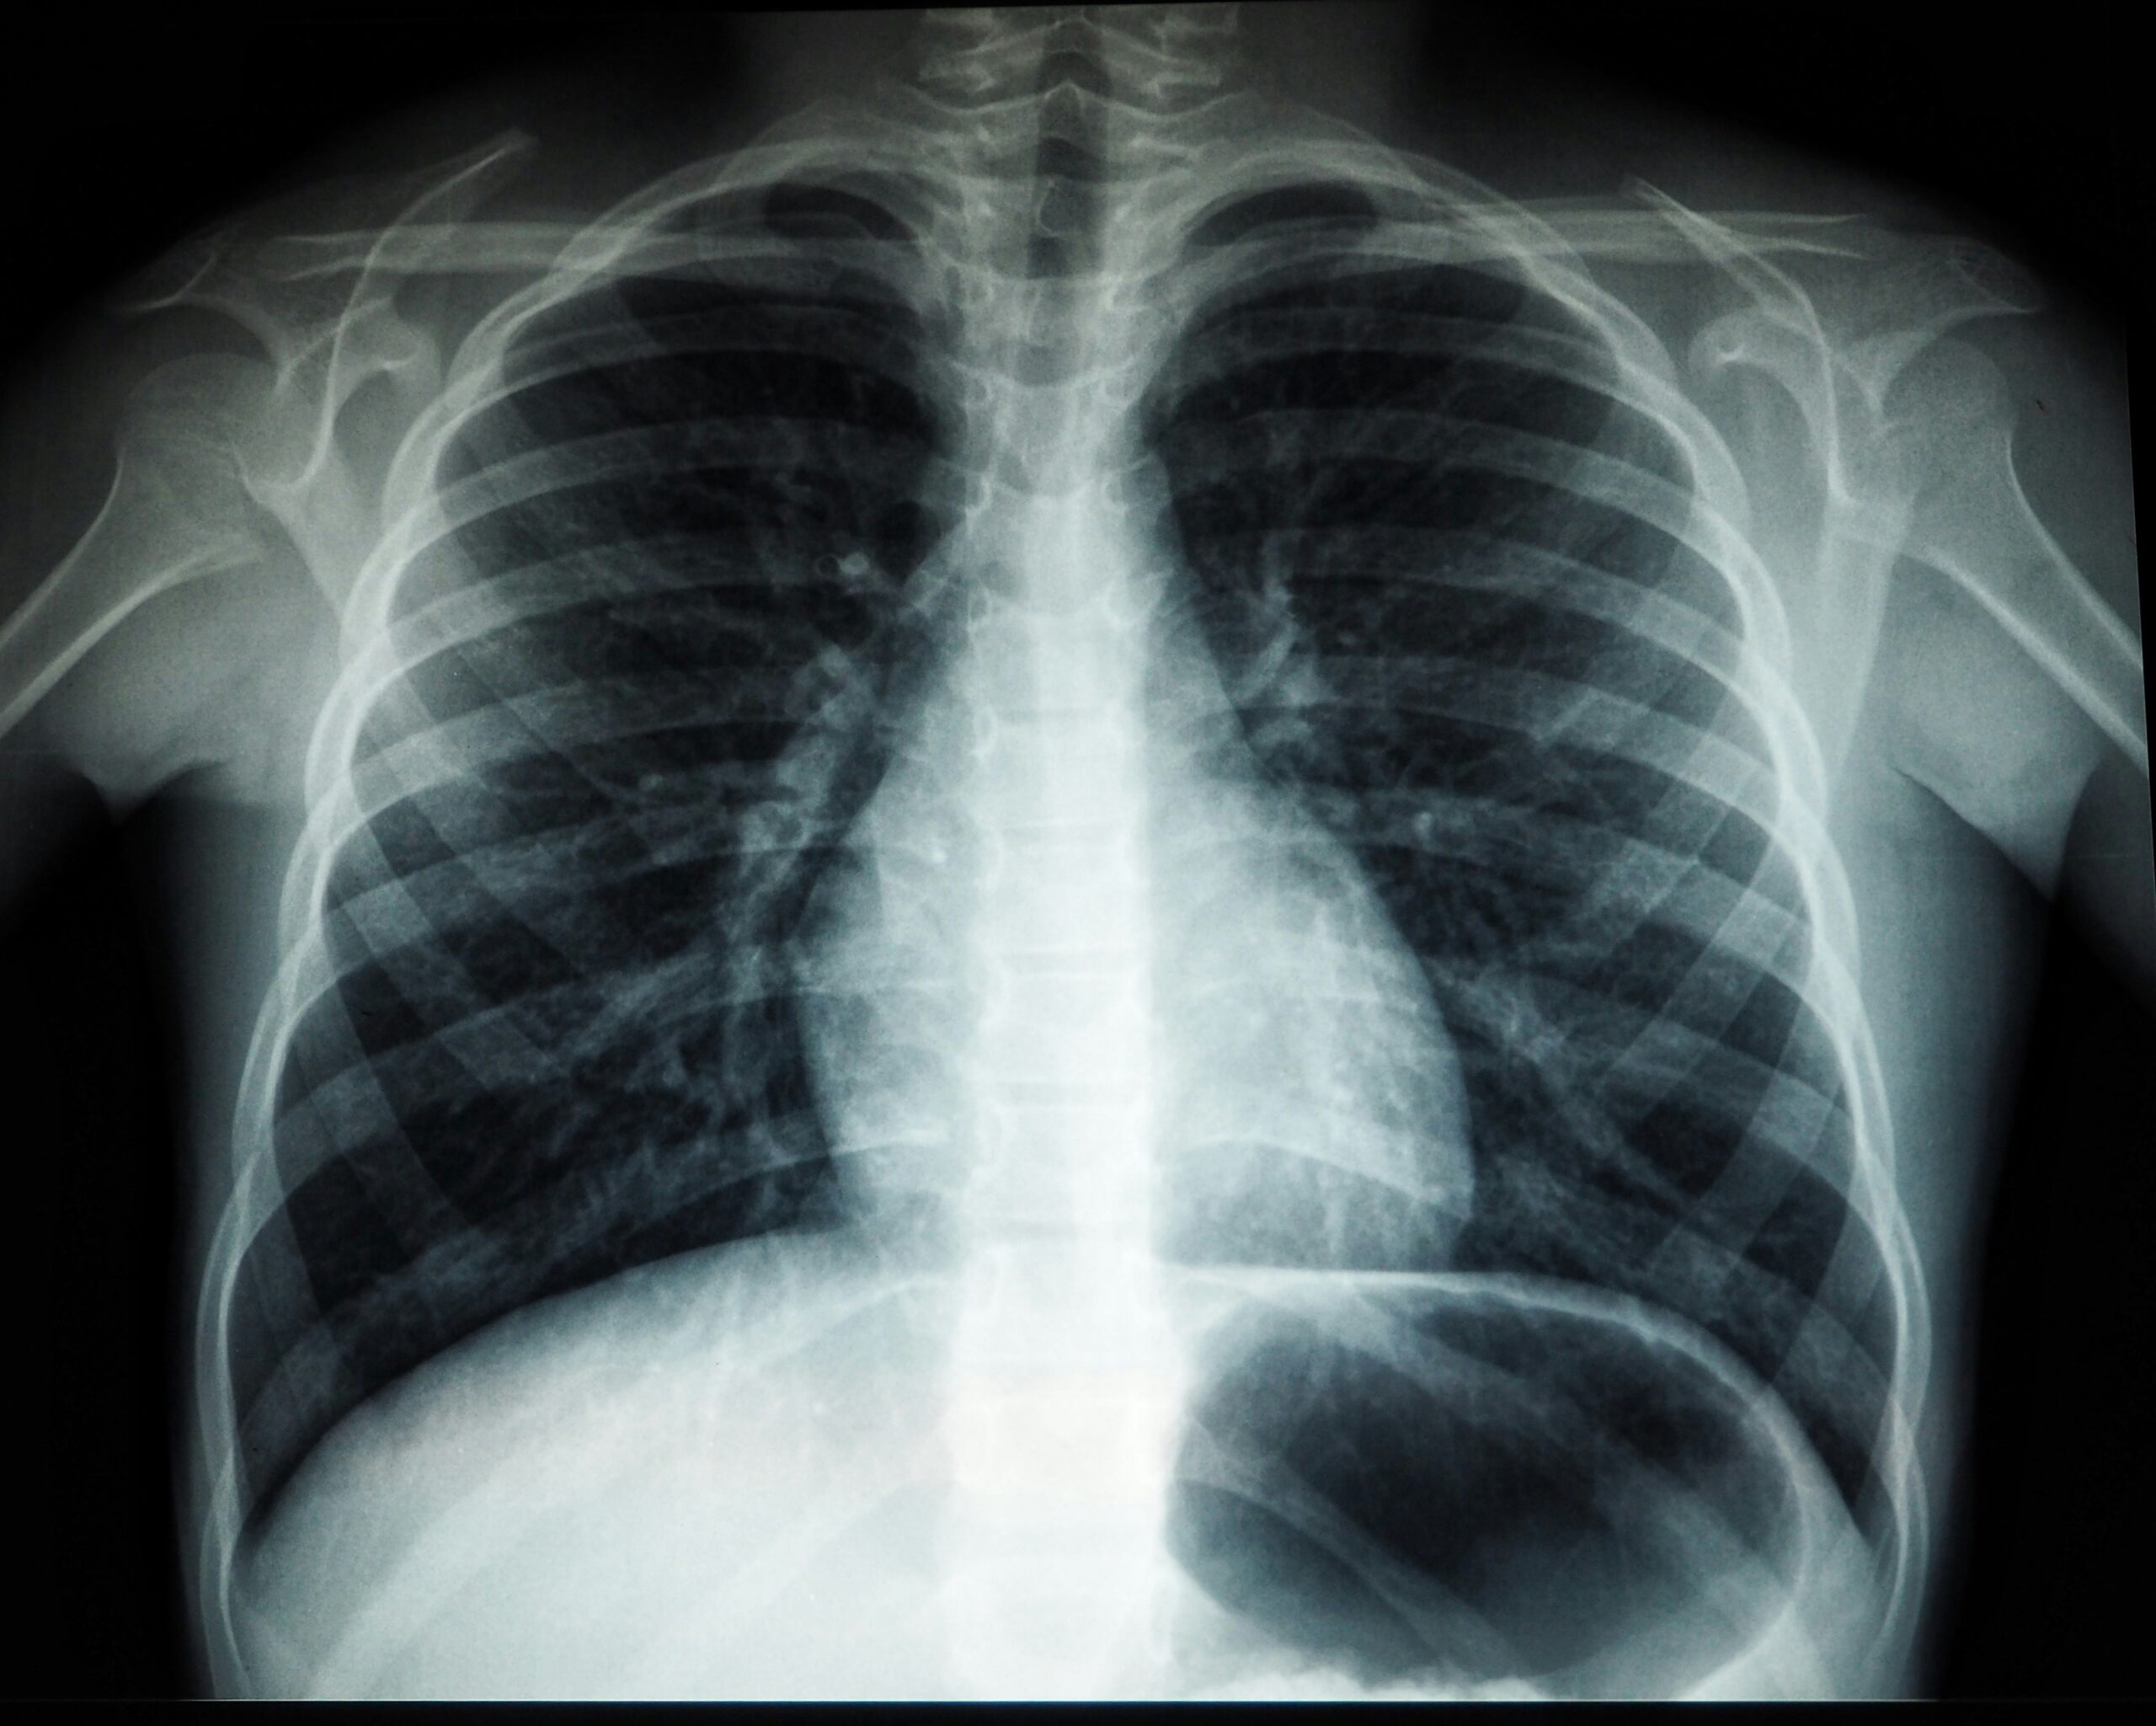

My ex, Ray, claimed he could see inside me. Your bones, he’d said on our first date. I’d assumed he was referring to my skeletal structure, perhaps complimenting me on high cheekbones or a soft jawline. But then one day he asked why I didn’t have the cavity in my left molar fixed. more